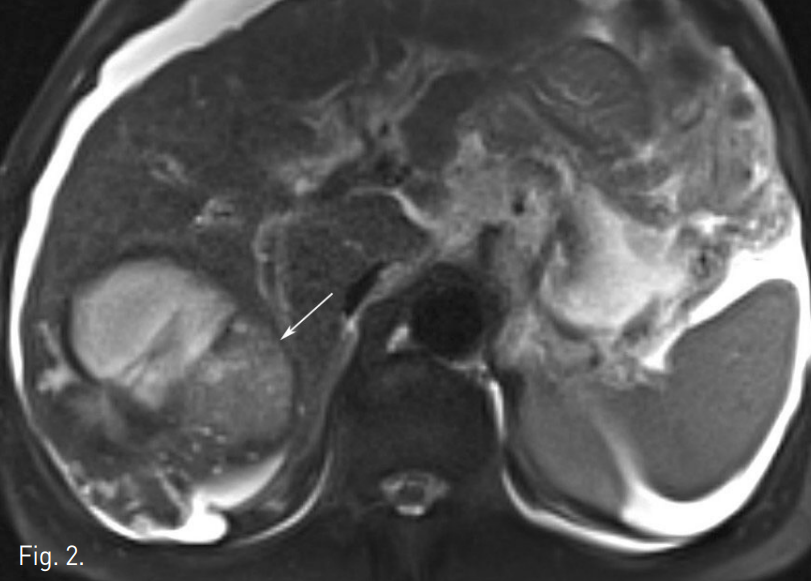

초음파 유도 하에 우측 대퇴동맥을 천자하여 5F vascular sheath를 삽입함. 5F RH catheter (Cook, Bloomington, USA)로 복강동맥을 선택한 후 시행한 동맥조영술에서 우간동맥 S7을 담당하는 분지동맥에서 기원하는 4cm 크기의 가성 동맥류가 관찰되었다(Fig. 3A). 먼저 RH catheter 내부에 2.2F microcatheter (Progreat, Terumo, Tokyo, Japan)를 삽입하여 가성 동맥류가 기원하는 혈관을 초선택하여 4개의 미세코일 (3mm x 2cm, Tornado embolization microcoil: Cook, Bloomington, IN, USA)을 이용해 색전하였다. 색전 후 시행한 동맥조영술에서 가성동맥류는 더 이상 조영되지 않았다. Coil 색전술 후 동맥조영술에서 인접하여 같은 분지동맥의 좀 더 근위부 동맥에 의해 공급받는 4.2cm 크기의 간세포암종으로 생각되는 비정상적인 과혈관성 병변이 좀 더 뚜렷하게 관찰되었다(Fig. 3B). 이후 과혈관성 병변을 공급하는 우간동맥의 분지동맥을 미세카테터로 초선택하여 항암제(Adriamycin 50mg)와 색전물질(Lipiodol 10cc)의 혼합물을 이용하여 화학색전술을 시행하였다. 화학색전 후 시행한 동맥조영술에서 종양이 조영되지 않고 내부가 lipiodol로 침착된 것 확인 후 시술을 종료하였다(Fig. 3C).

Fig. 3

A. Celiac arteriogram shows pseudoaneurysm with jet flow (arrow) from right posterior superior hepatic artery.

B. Right posterior hepatic arteriogram after coil embolization shows no extravasation with pseudoaneurysm. Hepatoma is supplied by just proximal arterial branches (arrow).